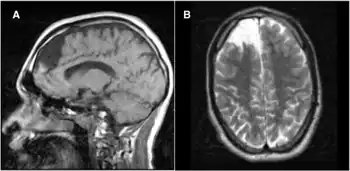

In many cases, propionic acidemia can damage the brain, heart, kidney, liver, cause seizures and delays to normal development such as walking or talking. The patient may need to be hospitalized to prevent breakdown of proteins within the body. Dietary needs must be closely managed.

- ↑ Hamilton RL, Haas RH, Nyhan WC, Powell HC, Grafe MR (1995). "Neuropathology of propionic acidemia: a report of two patients with basal ganglia lesions". Journal of Child Neurology. 10 (1): 25–30. doi:10.1177/088307389501000107. PMID 7769173. S2CID 12674920.